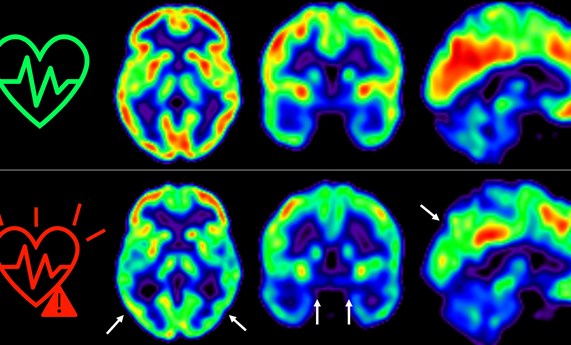

• CIBERSAM

Influencia de marcadores genéticos evolutivos relacionados con el neurodesarrollo fetal en la esquizofrenia

24/10/2023